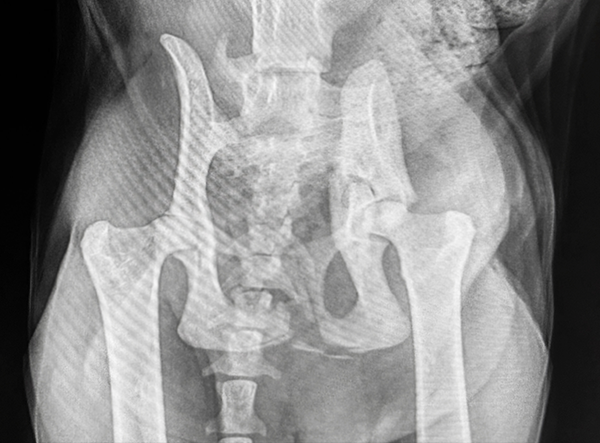

This feline patient presented with a severe pelvic trauma following high-impact trauma. Diagnostic imaging revealed a comminuted ilium and acetabulum fracture, along with sacroiliac (SI) luxation — a complex orthopedic challenge requiring careful reconstruction and stabilization.

Veterinary surgeon Dr. Matan Or (Israel) performed the repair using components from the LeiLOX 1.5 Locking Plate System, known for its precision, flexibility, and lightweight titanium construction.

Post-operative radiographs showed excellent alignment, secure implant positioning, and stable SI fixation. This multifaceted repair highlights the versatility of the LeiLOX system and the skill of the surgical team. The patient is recovering well with a positive long-term prognosis.